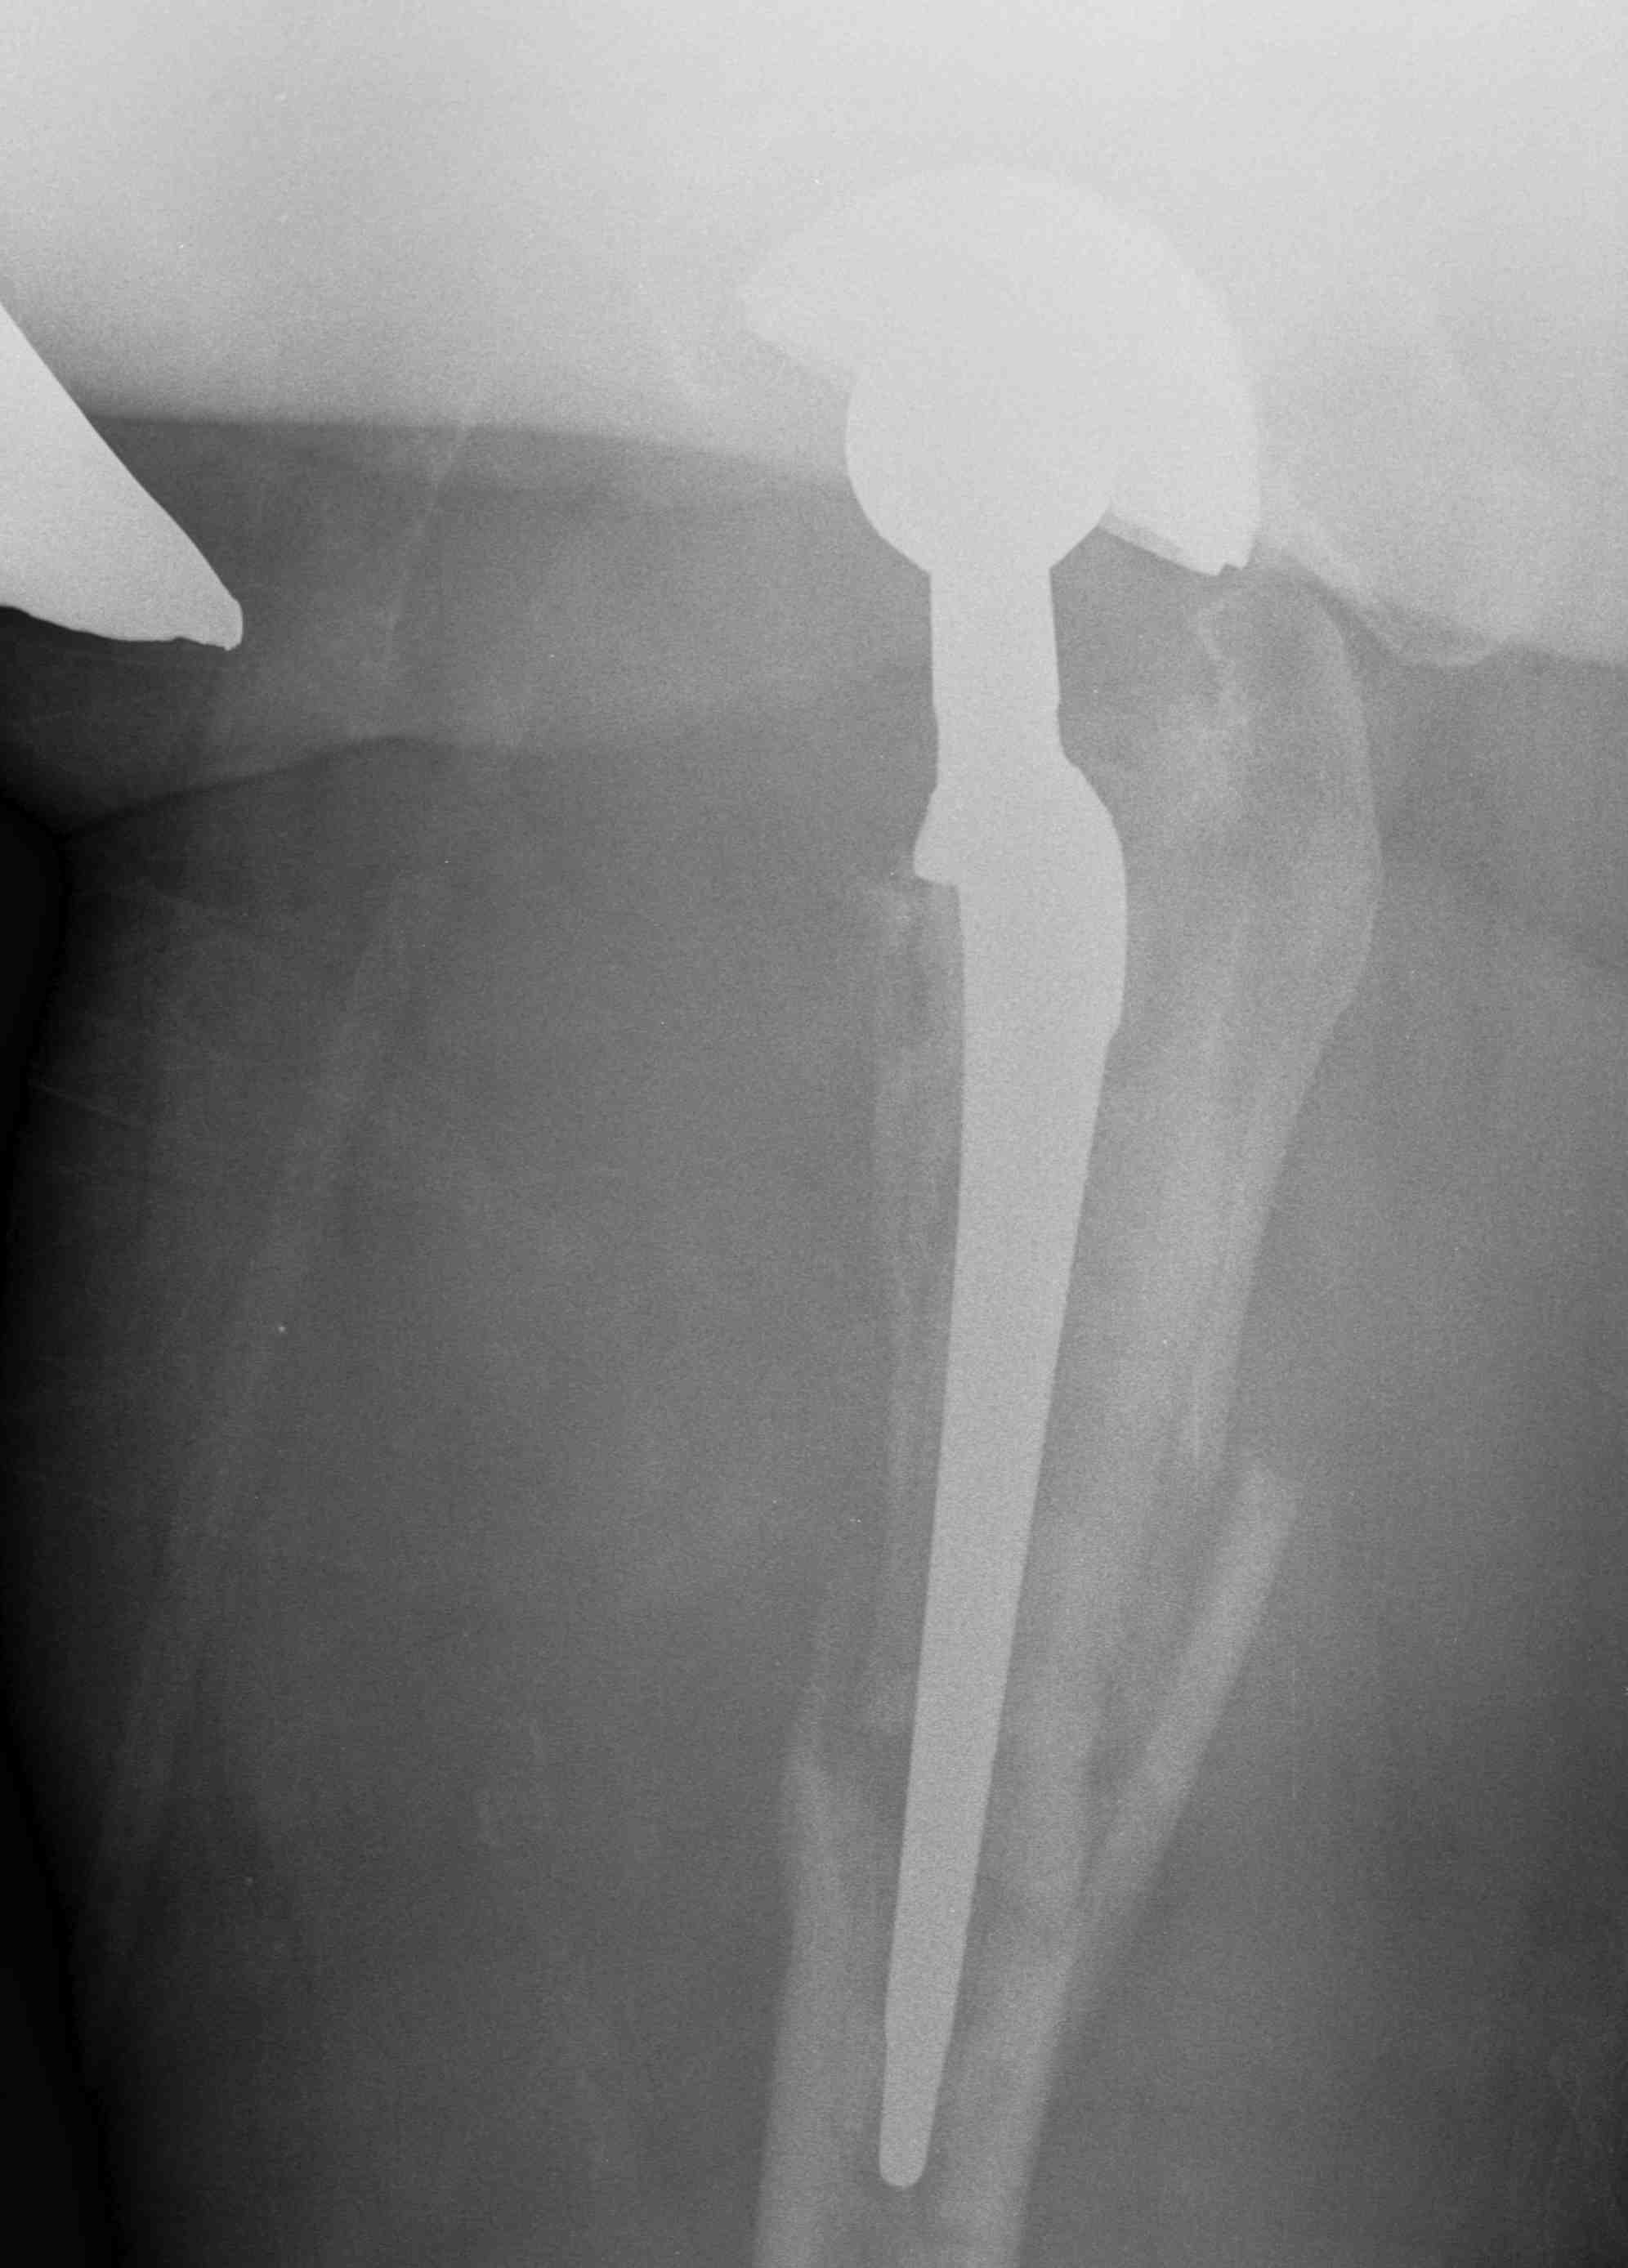

Long stem uncemented revision

Revision uncemented arthroplasty with Zimmer cable plate

Long stem uncemented revision with cortical strut allograft

Long stem uncemented revision with plate + cortical struts